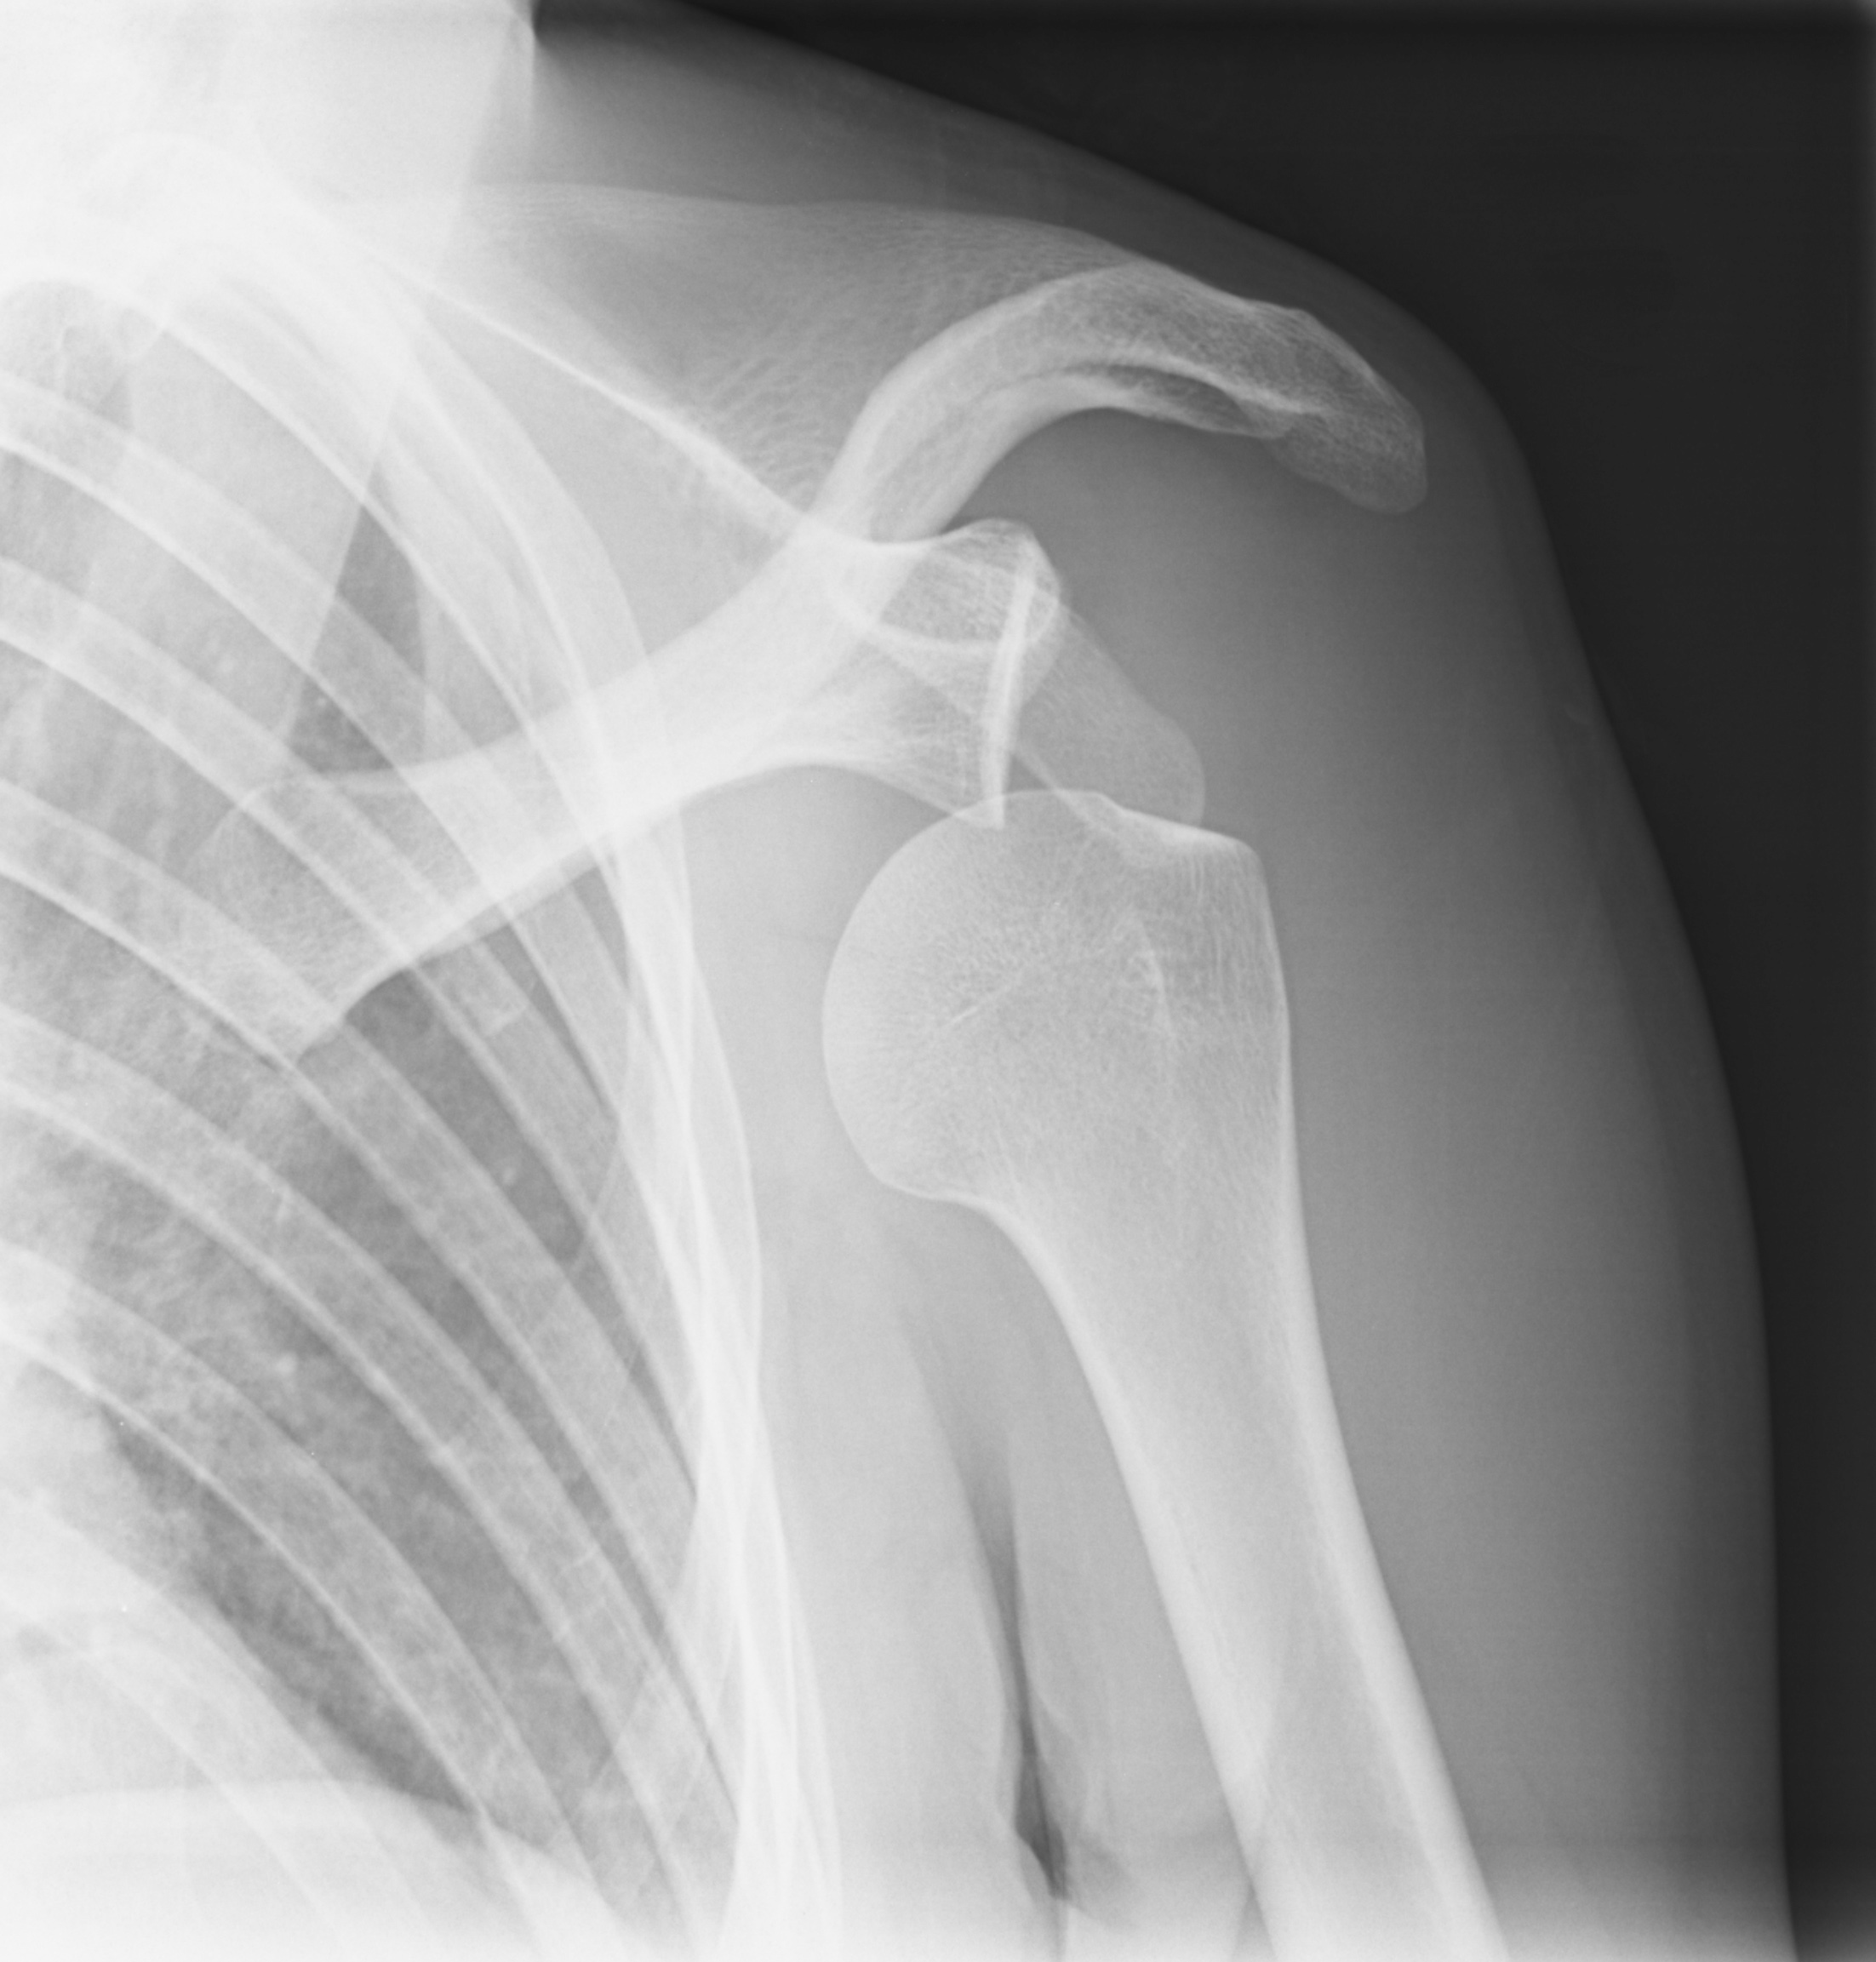

shoulder dislocation x-ray